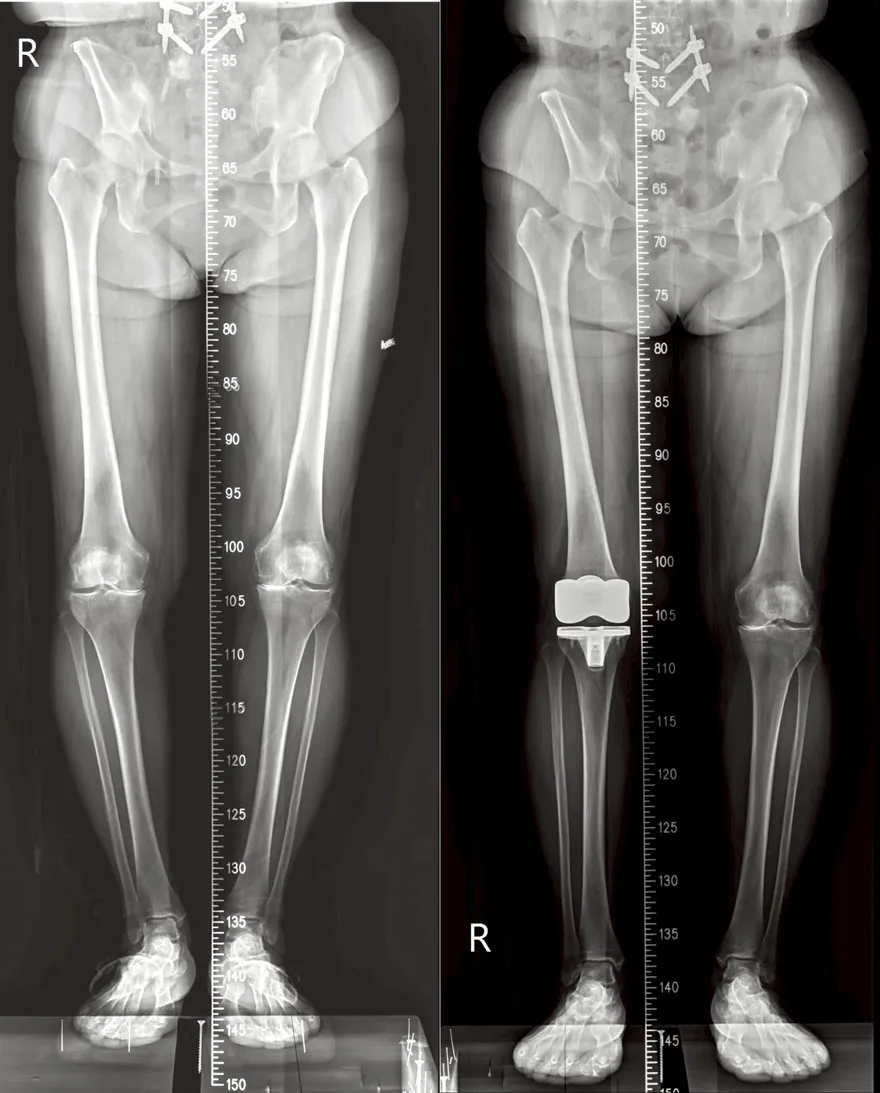

膝蓋磨到骨貼骨!打兩年玻尿酸無效 換人工關節才解決

全人工膝關節置換手術

鈦合金人工關節

人工關節墊片